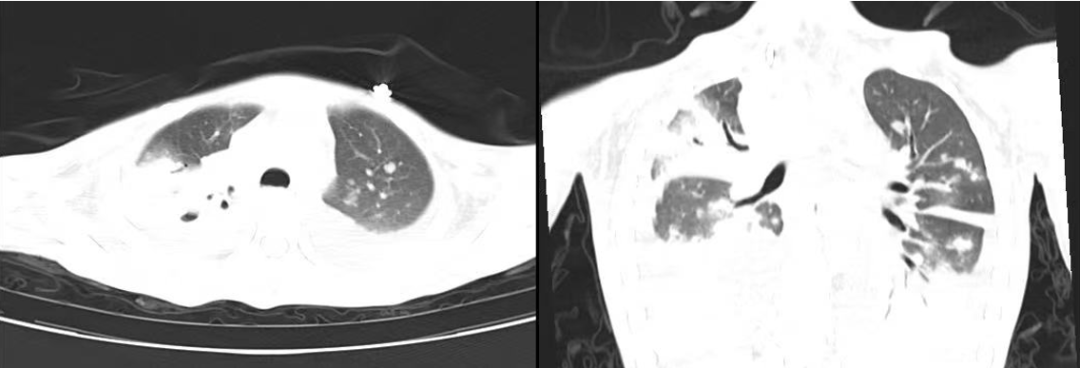

小月的肺部多发斑块影,累及多肺叶伴胸腔积液、肺空洞